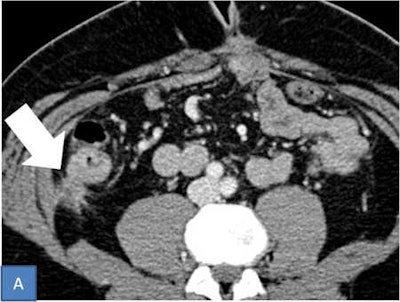

Ciolina wrote that peritoneal carcinosis is characterized by the presence of neoplastic implants with different morphological features and distribution in the peritoneal cavity. Radiologists must evaluate both morphology and localization. Solid, cystic, and mixed implants can present with different patterns that depict typical aspects of peritoneal carcinomatosis.

The micronodular pattern is characterized by the presence of tiny 1- to 5-mm milky spots of peritoneal implants diffusely involving the tunica serosa and subserosal fat. The greater omentum, lesser omentum, and mesentery are typically involved. Conversely, the nodular pattern is characterized by the presence of nodular implants larger than 5 mm diffusely involving the tunica serosa and subserosal fat. Nodules may have an oval shape with rounded contours or a star shape appearance with spiculated margins providing a stellate pattern, she pointed out.